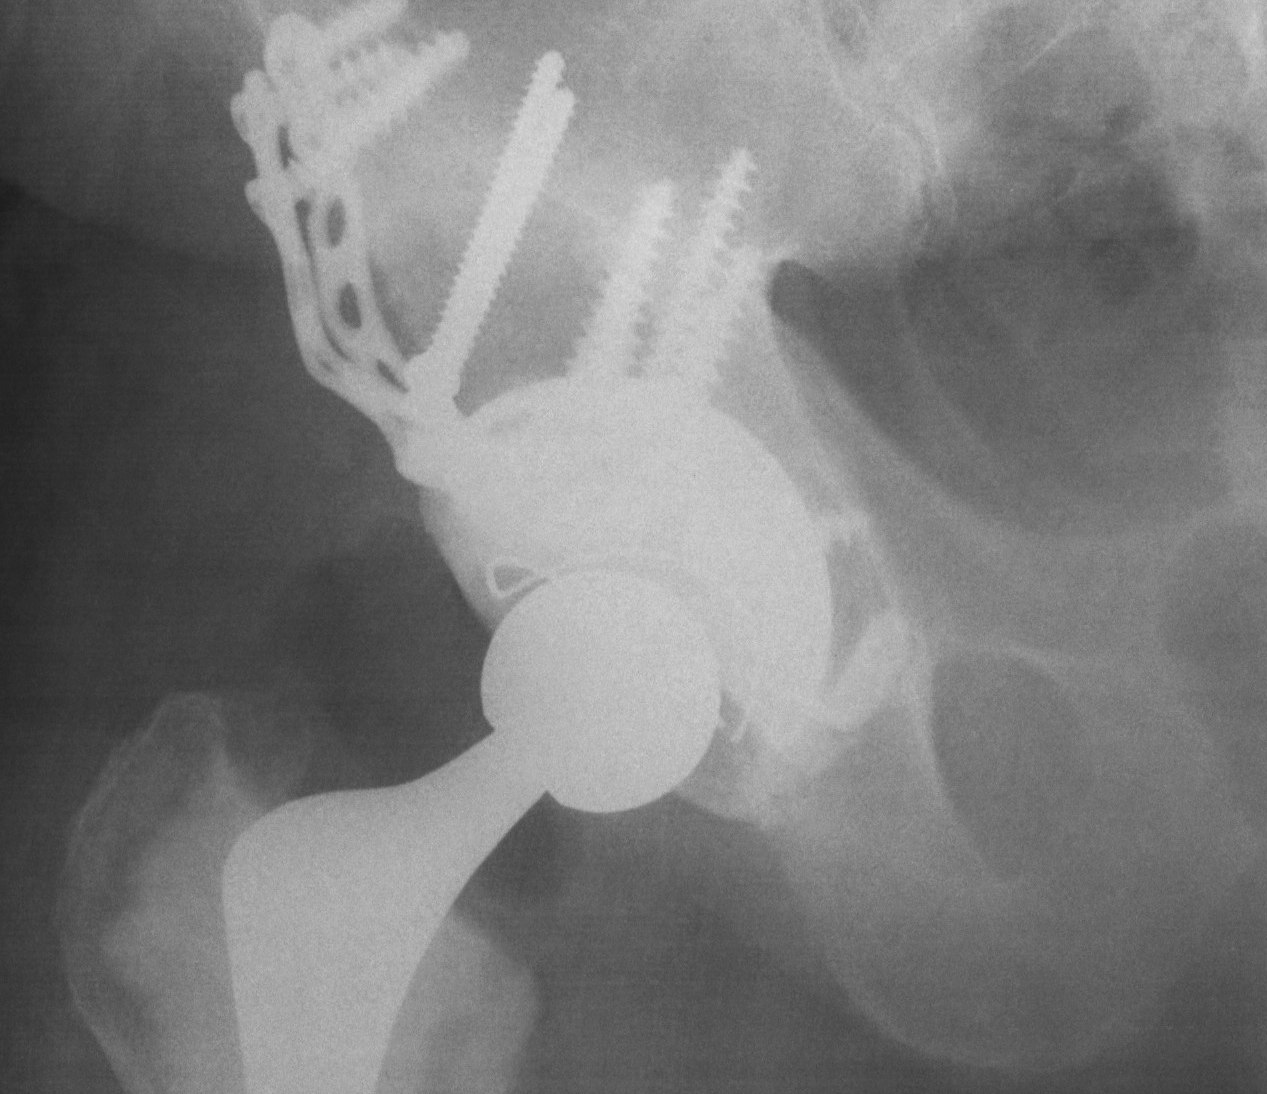

Option: Custom-made triflange components

CT guided model of pelvis

- custom made acetabular cage

- fits defect exactly

- flanges perfectly designed and not malleable to improve strength

- HA coated

- cement poly cup into it

Indications

- massive defects

Results

- 90% 4.5 year survival in complicated patients